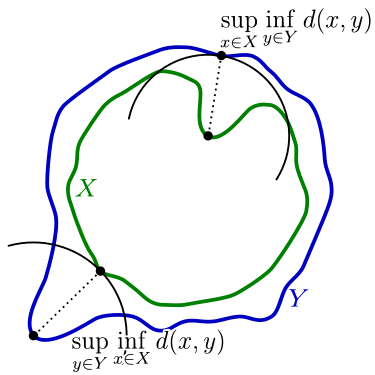

Hausdorff距离(HD95)

度量两个点集间的距离,判断预测边缘与真实边缘的差距

公式为: